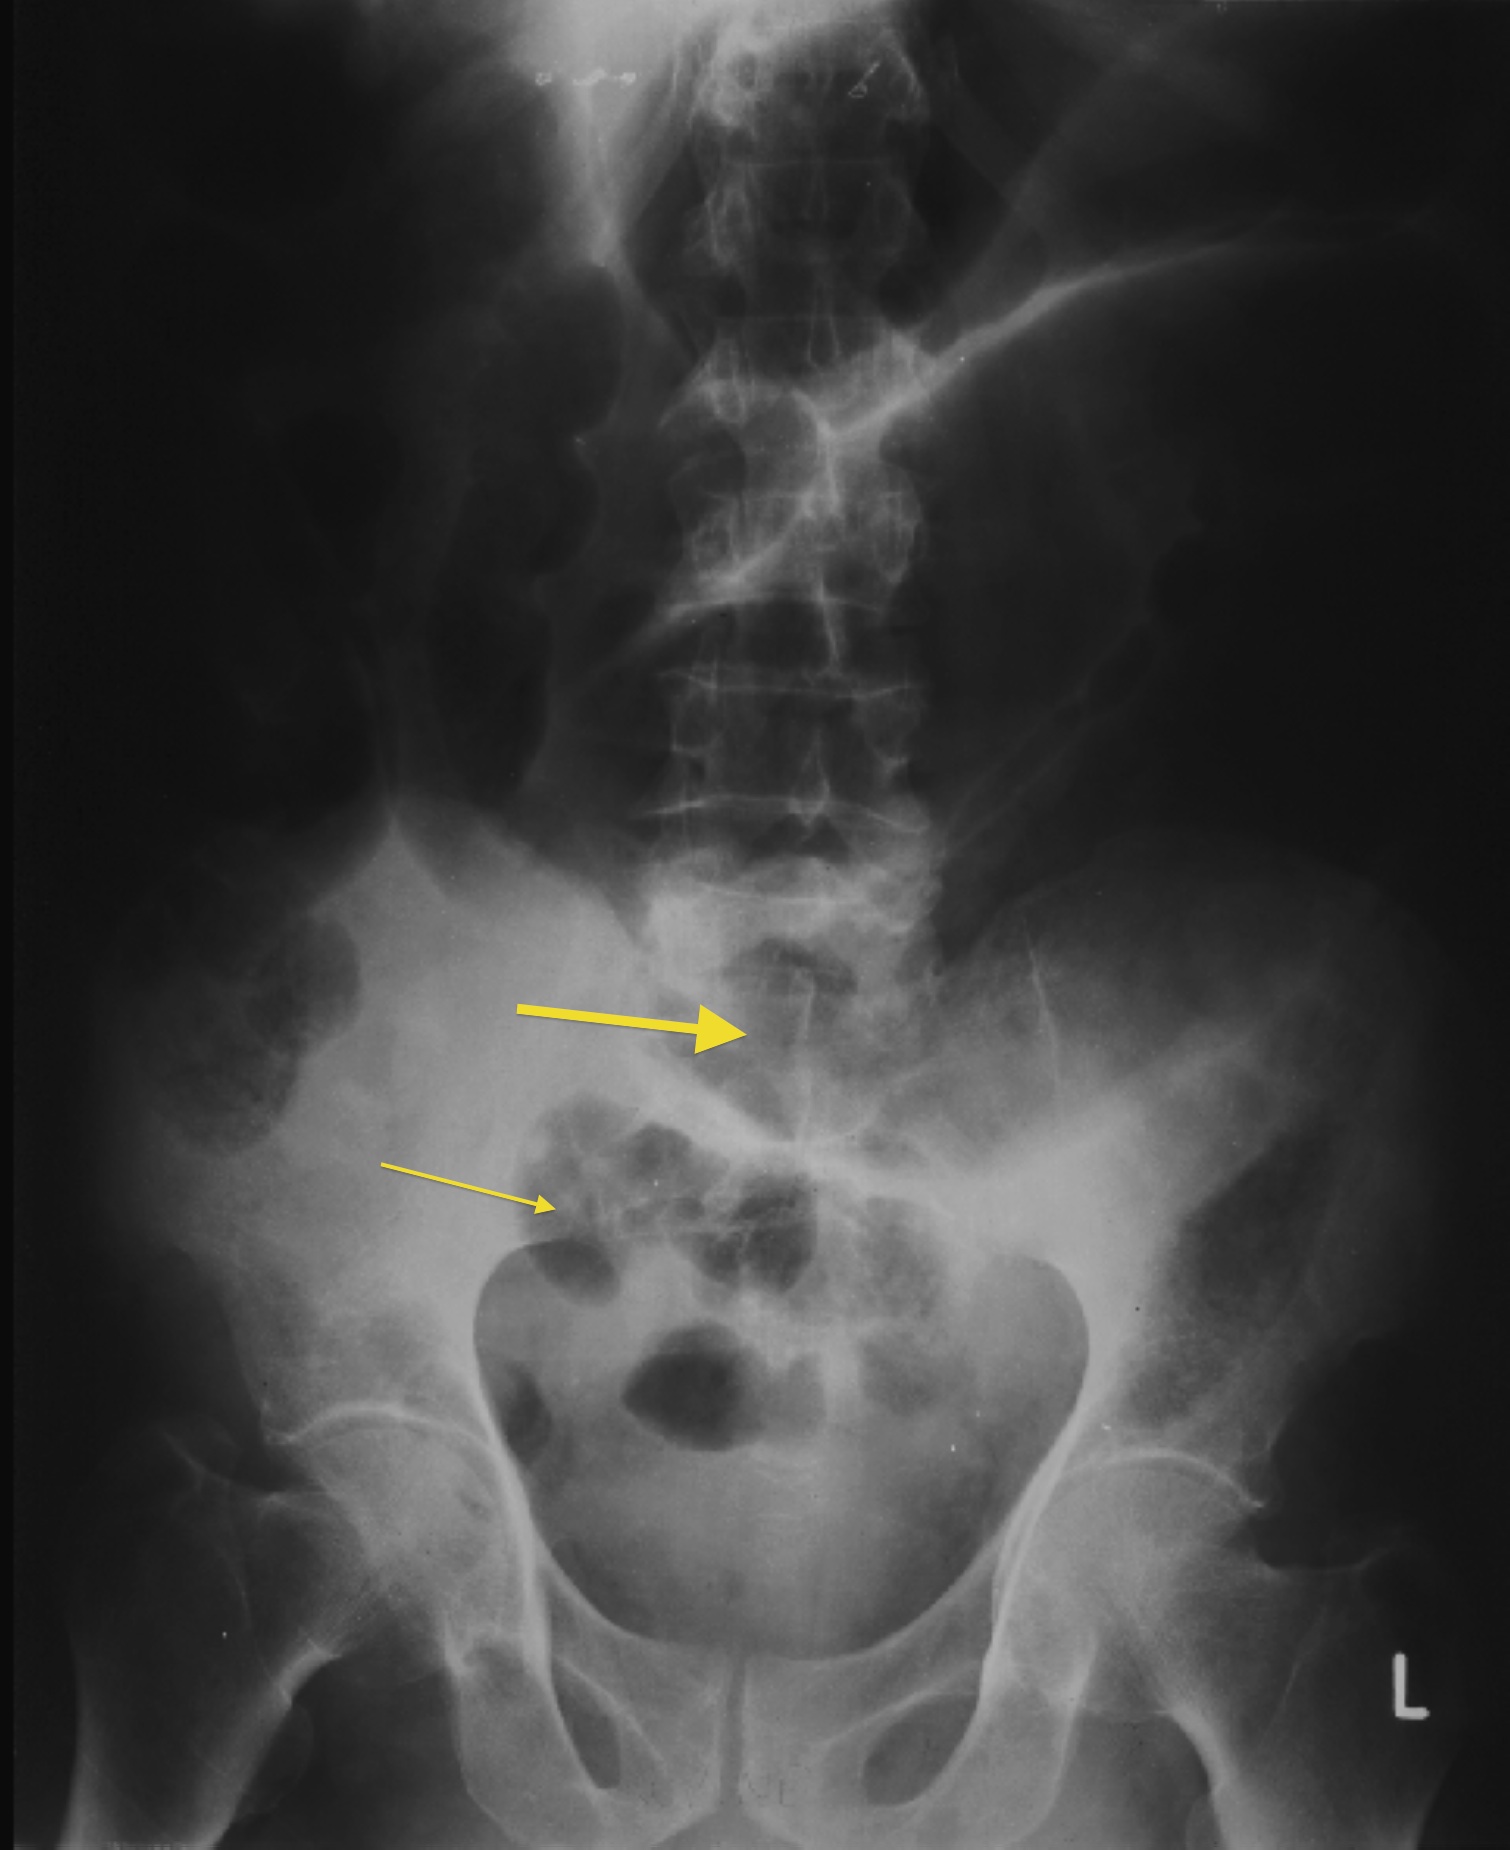

Small bowel obstruction is a common clinical presentation that presents a diagnostic conundrum. Over the last 2 decades, there has been a paradigm shift in the radiological investigation of small bowel obstruction (SBO) and in the indication for and timing of surgical intervention. Cross sectional imaging (predominantly computed tomography) has largely replaced the widespread use of radiographic small bowel follow-through studies as the imaging modality of choice for SBO. This article illustrates the current imaging modalities available for diagnosis of small bowel obstruction. (Full text available online at www.medpharm.tandfonline.com/ojfp) S Afr Fam Pract 2015; DOI: /10.1080/20786190.2014.977052